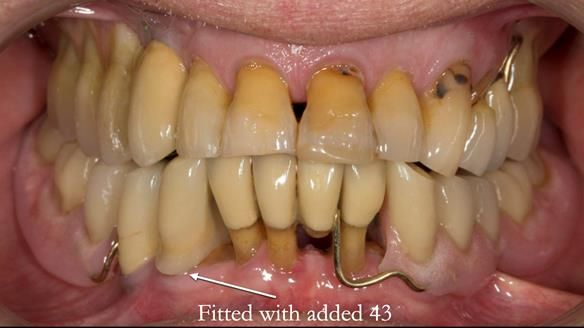

In 2022, tooth 43 fractured.

An artificial tooth was added to the RPD

by welding a cobalt–chrome tag to the bar

and adding the tooth.

The denture continued to function extremely well.

The way Rowan lengthened the teeth — particularly in the upper RPD — to match the existing gingival recession on the remaining teeth was superb. The dentures sit naturally within the context of the rest of the mouth.